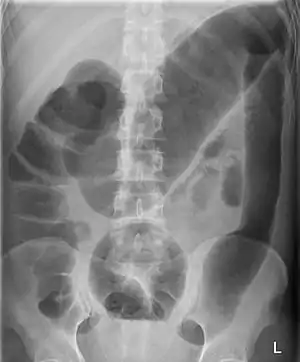

| Toxic megacolon associated with ulcerative colitis. | |

Toxic megacolon